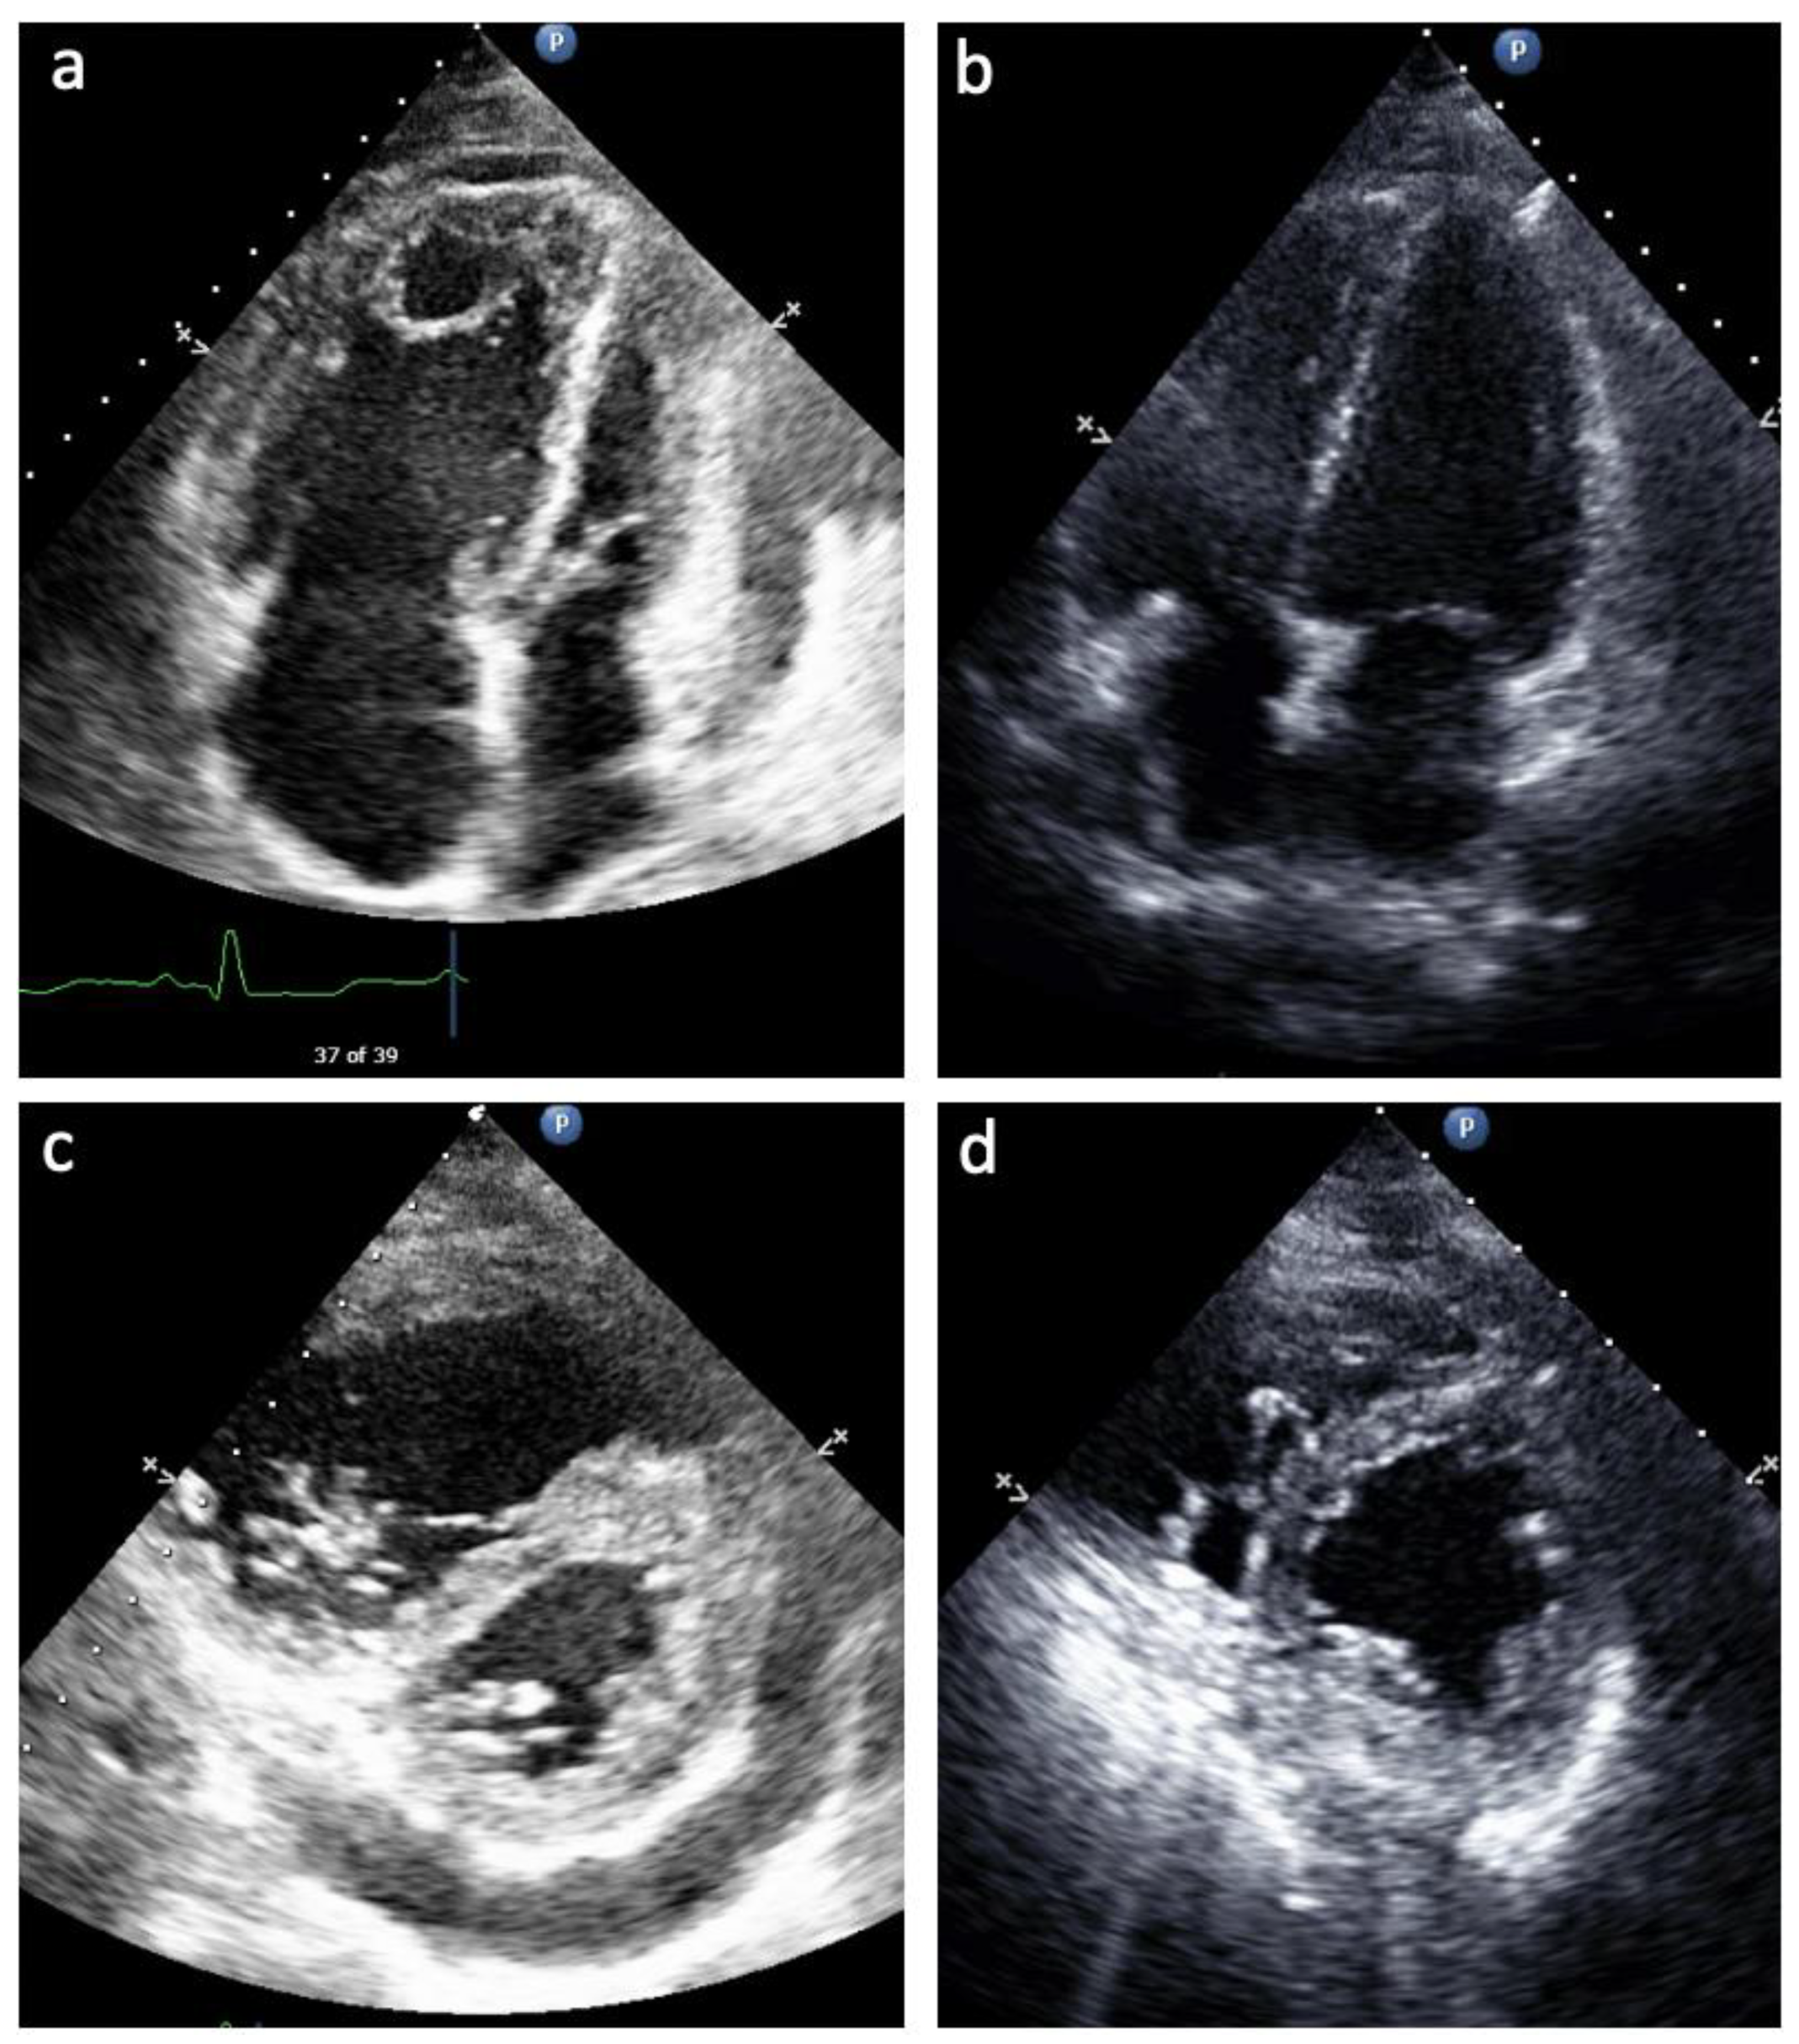

Table 4 summarizes the echocardiographic variables of the patients just before delivery, at an average of 34 weeks’ gestation. In six of the seven pregnancies, patients had either mild RV systolic dysfunction or normal RV systolic function as well as either mild or no TR. In six of the seven pregnancies, there was either no RVOT Doppler notching or only late Doppler nothing, consistent with a lower PVR. No patients during any of the pregnancies had a pericardial effusion at the time of delivery. As discussed above, Patient 3 presented initially at 28 weeks with severe RV dysfunction and clinical right heart failure. In the setting of PAH medical therapy titration through the remainder of her pregnancy, her RV dilation and dysfunction improved from severe to mild, TAPSE from 1.3 cm to 1.8 cm, septal flattening from severe to mild, TR from severe to none, and RVOT Doppler notching from mid notch pattern to no evidence of RVOT Doppler notching (Figure 1). Patient 6 had an improvement in RV size from moderate to mildly enlarged, with resolution of systolic septal flattening and RVOT Doppler notch with PAH therapy by the third trimester. Patient 1, on her second pregnancy, did experience worsening RV size, function, and worsening TR on her echocardiogram in the last week before delivery. While she had no clinical right heart failure before hospital discharge postpartum, in the two weeks thereafter, she demonstrated elevated JVP and lower extremity edema. Given her worsening right heart function and clinical right heart failure, we counseled the patient away from breast feeding to resume therapy with her endothelin receptor antagonist, in addition to her other PAH medical therapies.

In contrast, Patients 3 and 6 in our series were diagnosed with PAH in their third trimester of pregnancy, and thus were untreated for PAH to that point. Patient 3 presented with severe, decompensated right heart failure, severe RV dysfunction and severe TR. This patient was treated with intravenous treprostinil and a PDE5i starting at 28 weeks gestation, and by 34 weeks TAPSE had increased from 1.3 cm to 1.8 cm and the degree of TR had fallen from severe to none. In contrast, Patient 6 presented with only mild RV dysfunction and mild TR in spite of no baseline PAH medical therapy.

Figure 1. Echocardiogram from Patient 3 prior to (a,b) and after (c,d) PAH medication optimization. (a) Apical 4 Chamber view of enlarged RA and enlarged and hypertrophied RV with small and underfilled LV, LA; (c) Apical 4 Chamber view of normalized RA and RV size and function on PAH therapy; (b) Parasternal short axis view of severe systolic septal flattening, RV enlargement and hypertrophy, and pericardial effusion; (d) Parasternal short axis view of resolution of systolic septal flattening and pericardial effusion with smaller RV size.